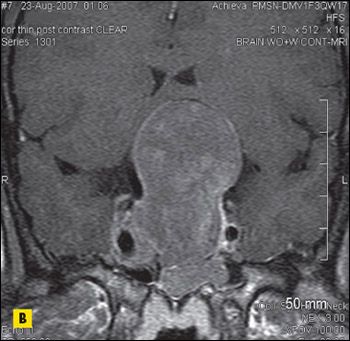

For several years, an asymptomatic, firm, nontender mass had been growing on the neck of a 54-year-old-man, slightly left of midline at the level of the hyoid bone. Thyroid function tests were normal. What does it indicate?